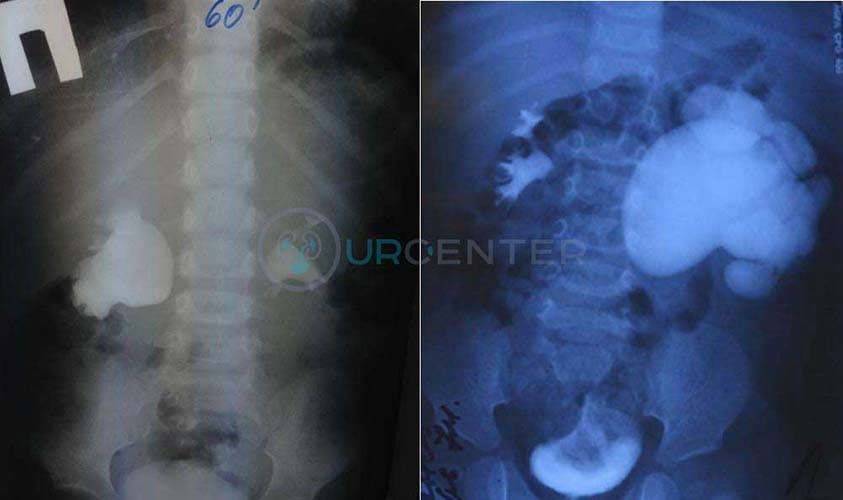

Экскреторная урография необходима для визуализации чашечно-лоханочной системы почки, определения нарушения оттока мочи. При этом после биохимического исследования крови (мочевина, креатинин) внутривенного вводится йодсодержащий контраст в возрастной дозировке и выполняется серия снимков. На снимках определяется коллекторная система почки, мочеточник, мочевой пузырь. По степени расширения лоханки и чашечек, а так же по времени контрастировани полостей и скорости выведения контраста судят о выраженности гидронефроза.

Рентгенографию выполняют с внутривенным контрастированием. Во время исследования оценивается функция почек, видно, как контрастное вещество проходит чашечки и лоханки, где накапливается, сколько времени нужно для полной фильтрации крови (экскреторная урография). В некоторых случаях контраст вводят снизу через мочеточник, что позволяет визуализировать уровень сужения (ретроградная уретеропиелография). В качестве диагностики применяется также , , радиоизотопное исследование. Уточнить все детали, увидеть воочию сужение перед операцией позволяет эндоскопическая уретероскопия (исследование при помощи эндоскопа, который вводится через мочеиспускательный канал и мочевой пузырь в мочеточник).